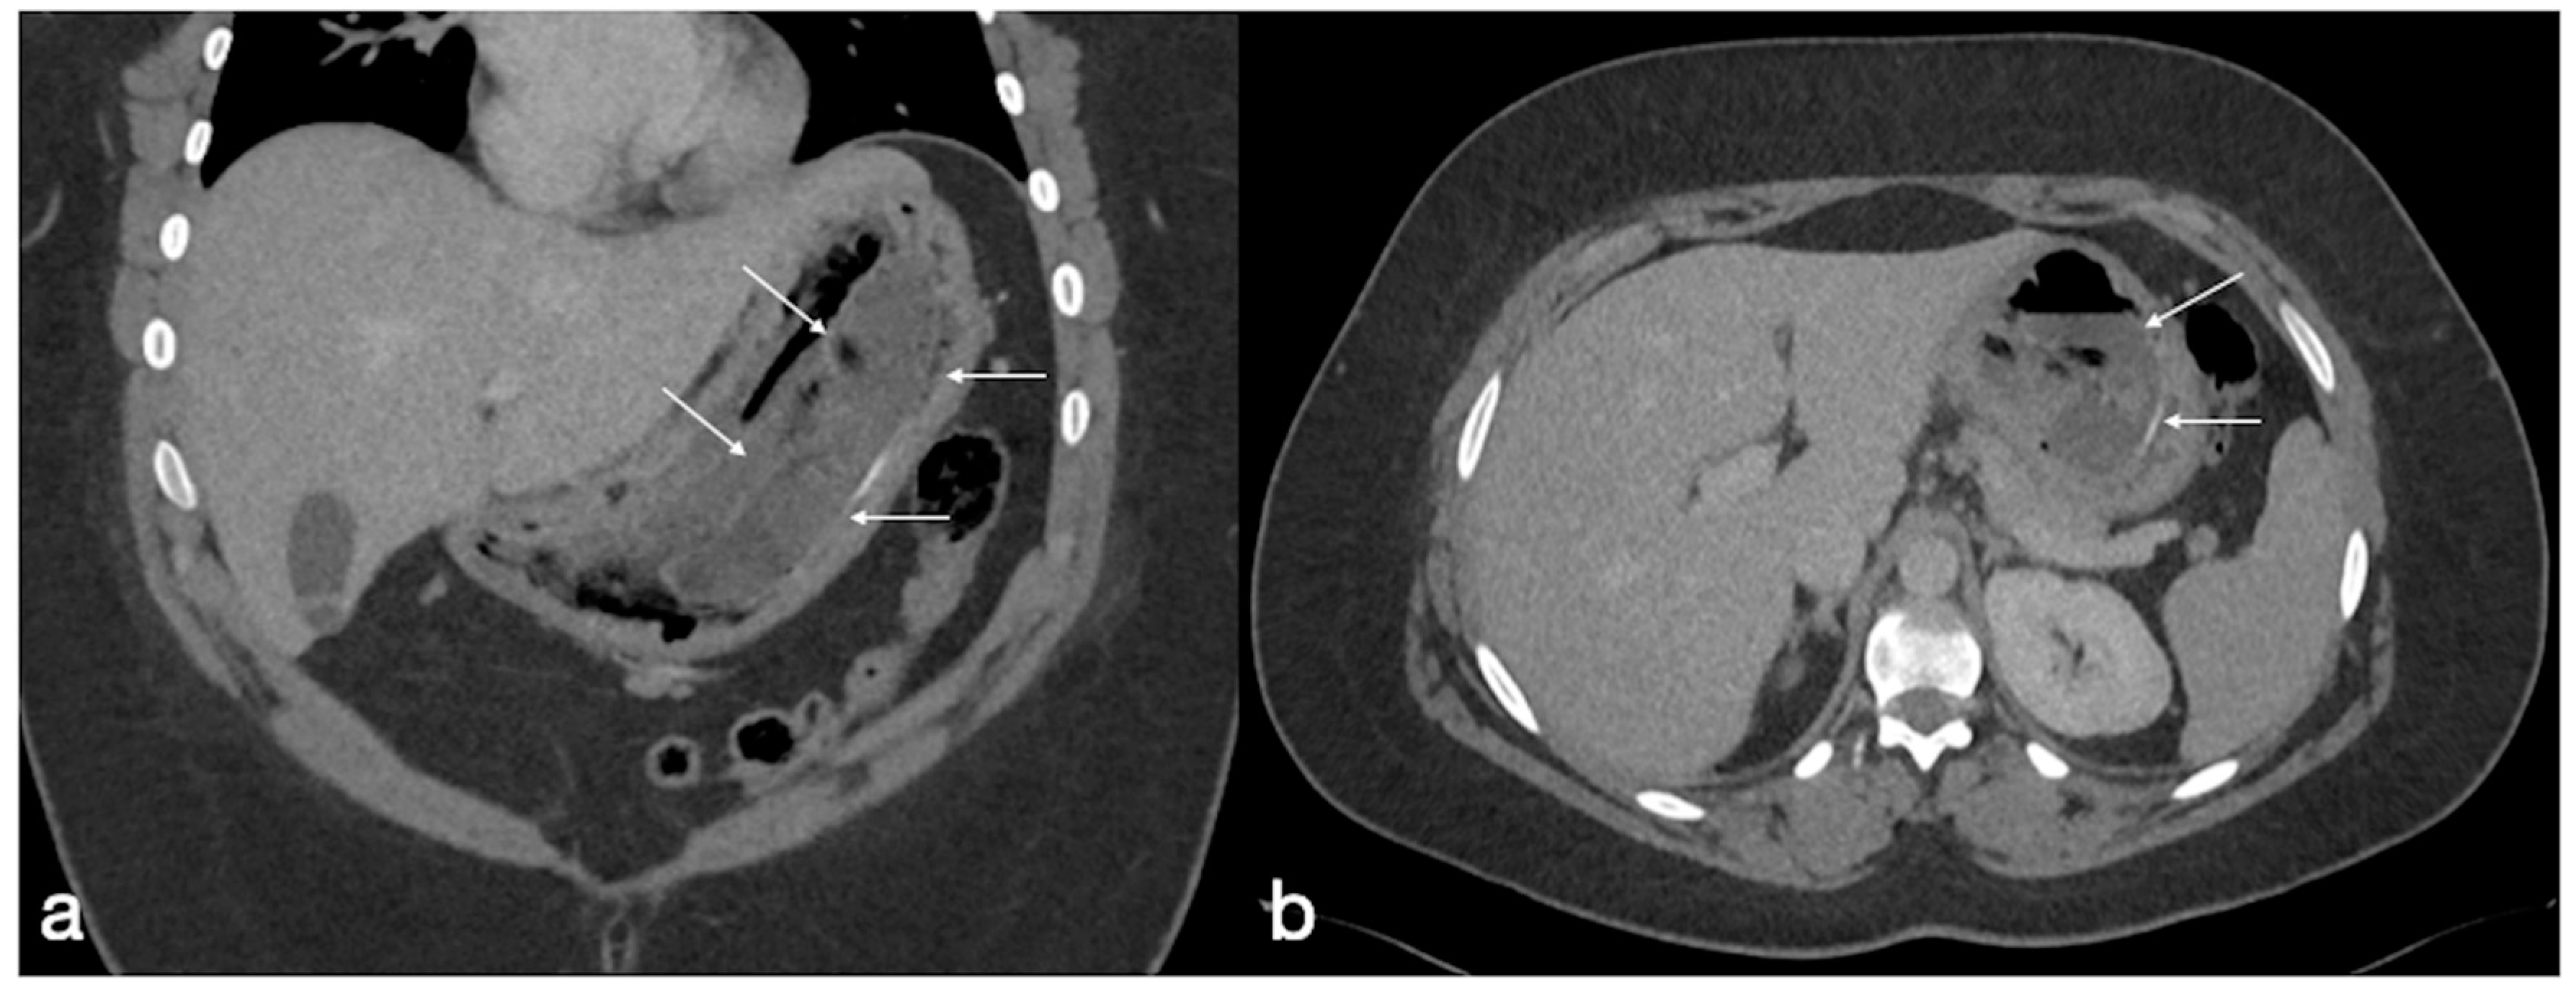

Figure 19. Patient 1. Porto-spleno-mesenteric venous thrombosis and colonic ischemia after sleeve gastrectomy. A 37-year-old female patient underwent sleeve gastrectomy. The patient came to the emergency department complaining of abdominal pain and fever. See the surgical gastric suture (a, coronal oblique view), the enlarged and thrombosed spleno-portal lumen (b, axial view; c, coronal oblique view, straight arrows), the consequential mesenteric congestion (d, axial view; e, coronal view, curved arrows), and the colonic ischemia (d, axial view; e, coronal view, circles). In the coronal view (e), the thrombosis that extends to the superior mesenteric vein lumen can be seen best. The patient was treated with multiple session of transhepatic catheter-directed thrombolysis.